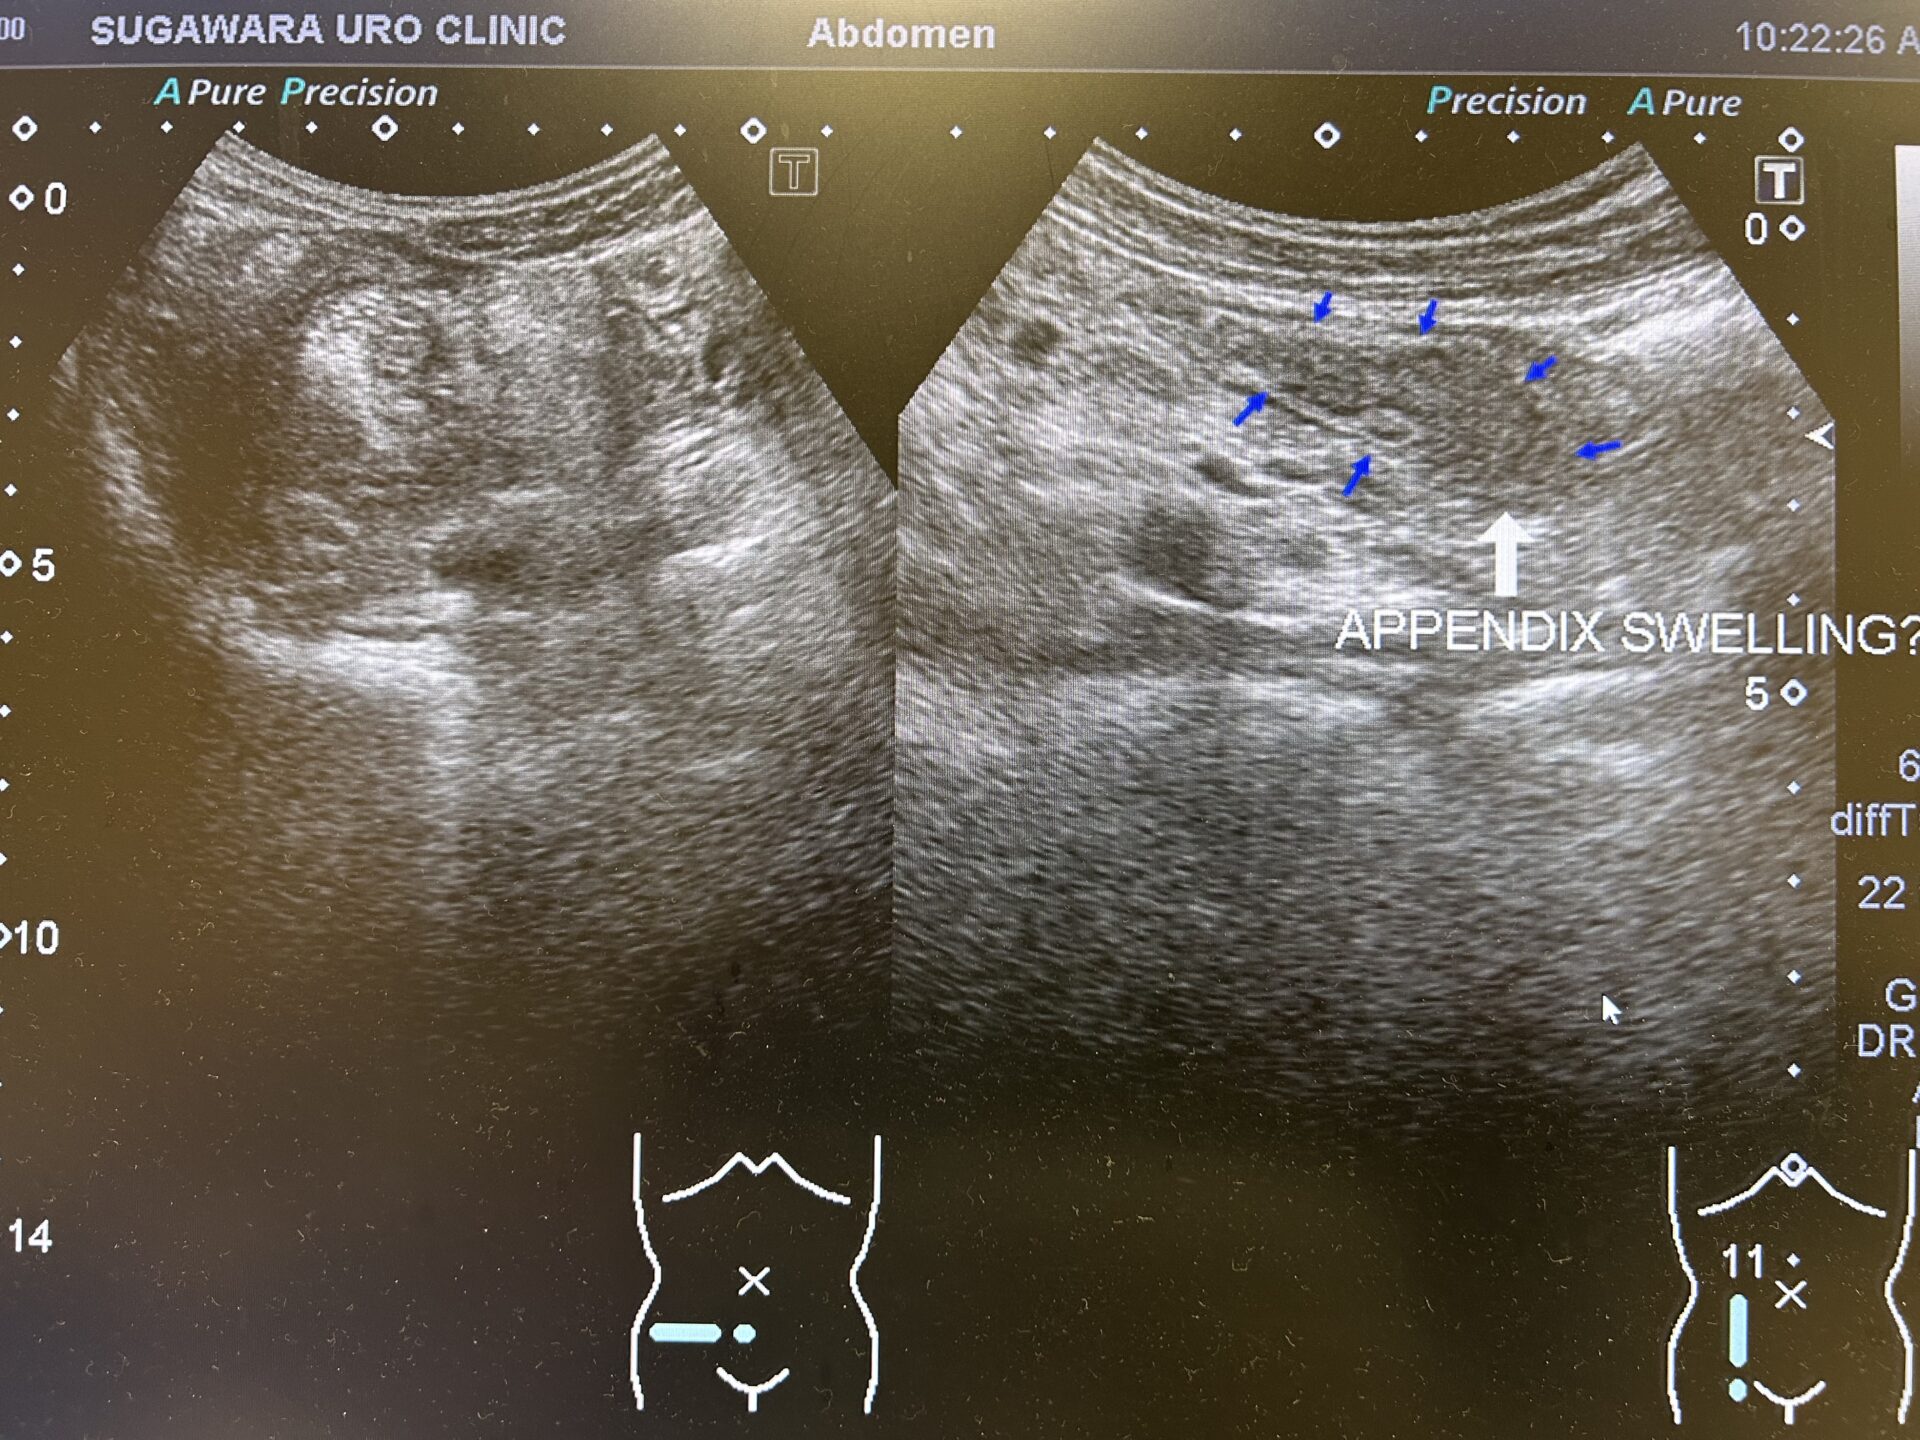

排尿時痛を伴った急性腹症”急性前立腺炎か急性虫垂炎かで診断に苦慮した一例”